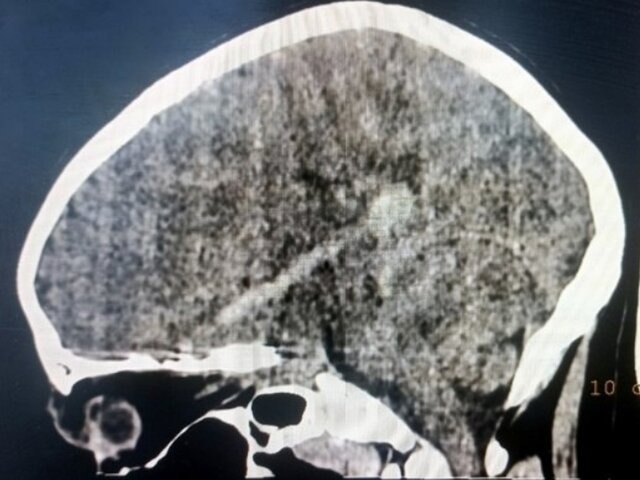

В результате проведенного обследования медики диагностировали открытую проникающую рану головы и головного мозга, ушиб головного мозга, внутримозговую гематому вдоль полости раневого канала, перелом основания черепа и параорбитальную гематому слева.

Фото: министерство здравоохранения Кировской области/